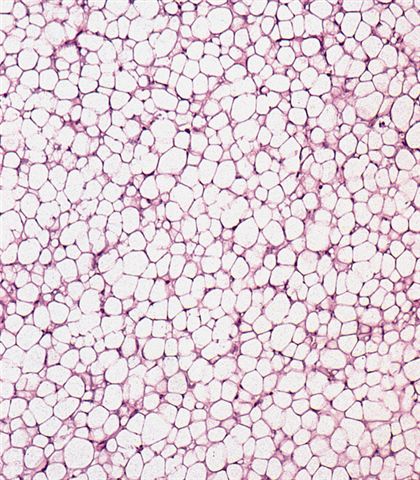

- Low grade

- Paucicellular with monomorphic, stellate or fusiform shaped cells without atypia; striking in their blandness, so much so that any significant pleomorphism should cause one to pause

- Prominent plexiform vasculature (delicate thin walled arborizing and curving capillaries that form a network reminiscent of chicken wire fencing)

- These are striking because of the overall background paucicellularity and are still present in high grade tumors but are much less obvious

- Numerous signet ring lipoblasts, particularly at periphery of lobules

- This imparts a lipoblastoma-like appearance (see Differential diagnosis)

- Mucoid matrix is rich in hyaluronic acid that may form large mucoid pools (so called pulmonary edema pattern)

- Will be positive for stromal mucin stains such as Alcian blue (see Microscopic (histologic) images)

- Can contain large areas of mature adipocytic differentiation